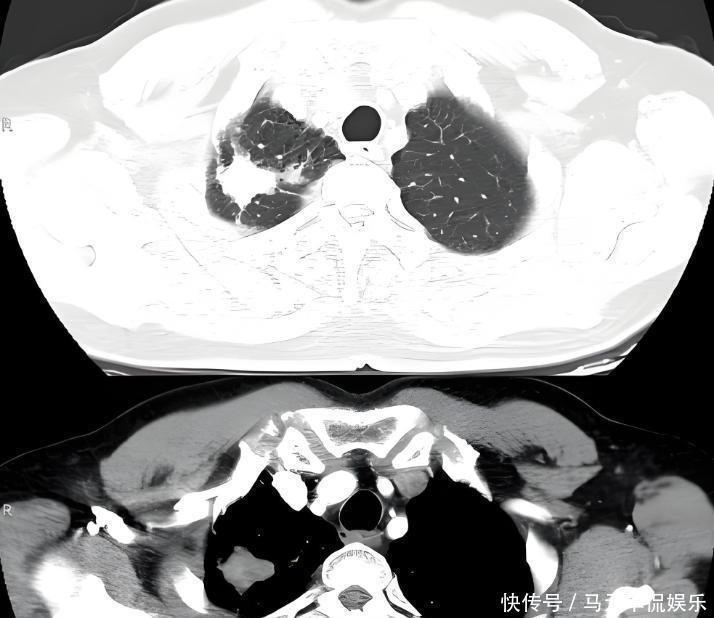

即便三四年前发现肺部结节,医生的警告他也没放在心上。甚至自嘲魔术师肺里有点雾很正常。更让人揪心的是,他的家族有着肺癌遗传史。

他的叔叔就因肺癌离世,双重风险下,他依旧没能戒掉烟瘾。2024年春节前夕,刘谦在体检中被查出肺部有大片阴影。进一步检查后,“肺腺癌”的诊断结果如同晴天霹雳砸在他头上。